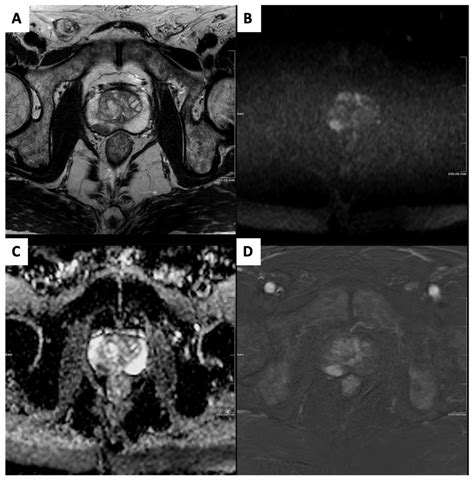

When you undergo an MRI of prostate, you are likely receiving a multiparametric examination. This means the scan captures data using several different sequences, each providing a unique perspective on the prostate’s health:

• T2-weighted imaging: Provides high-resolution anatomical images, allowing the radiologist to see the shape and size of the prostate clearly.

• Diffusion-weighted imaging (DWI): Measures the movement of water molecules within the tissue; cancerous cells, being more densely packed, restrict this movement, which shows up as a “bright spot” on the scan.

• Dynamic Contrast-Enhanced (DCE) imaging: Involves the injection of a contrast dye to observe how blood flows into the tissue, as tumors often exhibit distinct blood vessel patterns compared to normal tissue.

The combination of these sequences creates a comprehensive view that significantly increases the sensitivity and specificity of the diagnosis.